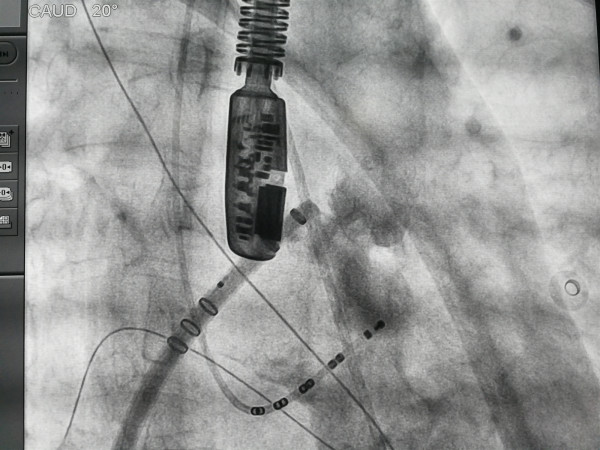

会议在山东省立医院宋尚明教授和内蒙古自治区人民医院王智勇教授的主持下开始了。在专家们正式进行高效消融进行交流前,内蒙古自治区人民医院副院长赵兴胜特意为此次直播会议致辞,赵兴胜副院长表示此次高效消融直播交流会意义重大,能够邀请到全国优秀的专家教授共同进行高效消融学术交流,是一次非常难得的机会,最后,赵兴胜副院长预祝会议圆满成功。高效消融直播交流会正式开始,专家们针对高效消融单中心经验、高效消融对手术成功率和效率的影响进行了分享和讨论,同时会议聚焦剖析了高效消融的临床获益,专家们对高效消融安全性问题进行问答和讨论,例如如何预防POP发生?灌注量不同对消融损伤形态及大小的影响关系等等。我院职工纷纷通过现场和在线方式聆听专家们的解答。值得一提的是,在此次高效消融直播交流会上,内蒙古自治区人医院王智勇团队通过直播平台,在线进行了房颤射频消融治疗及左心耳封堵一站式手术的演示,与全国专家针对房颤射频消融手术的技术和方法进行了分享,对如何降低患者的复发率展开了讨论。在线观看手术演示高达1460人。内蒙古自治区人民医院王智勇团队在自治区开辟了房颤射频消融治疗及左心耳封堵一站式手术的先河,房颤射频消融治疗及左心耳封堵一站式手术不仅节省了患者因术后复发房颤长期服用新型口服抗凝药物的经济负担,同时也大大减少了许多患者做完心脏射频消融术后,因血栓问题再次做左心耳封堵术,这样二次手术对血管造成损伤的问题发生。在线手术演示顺利完成,专家们对内蒙古自治区人民医院王智勇团队纷纷表示认可和赞扬,王智勇主任也非常激动地说,希望通过此次在线手术演示,也能够与全国知名专家互相学习,互相借鉴。